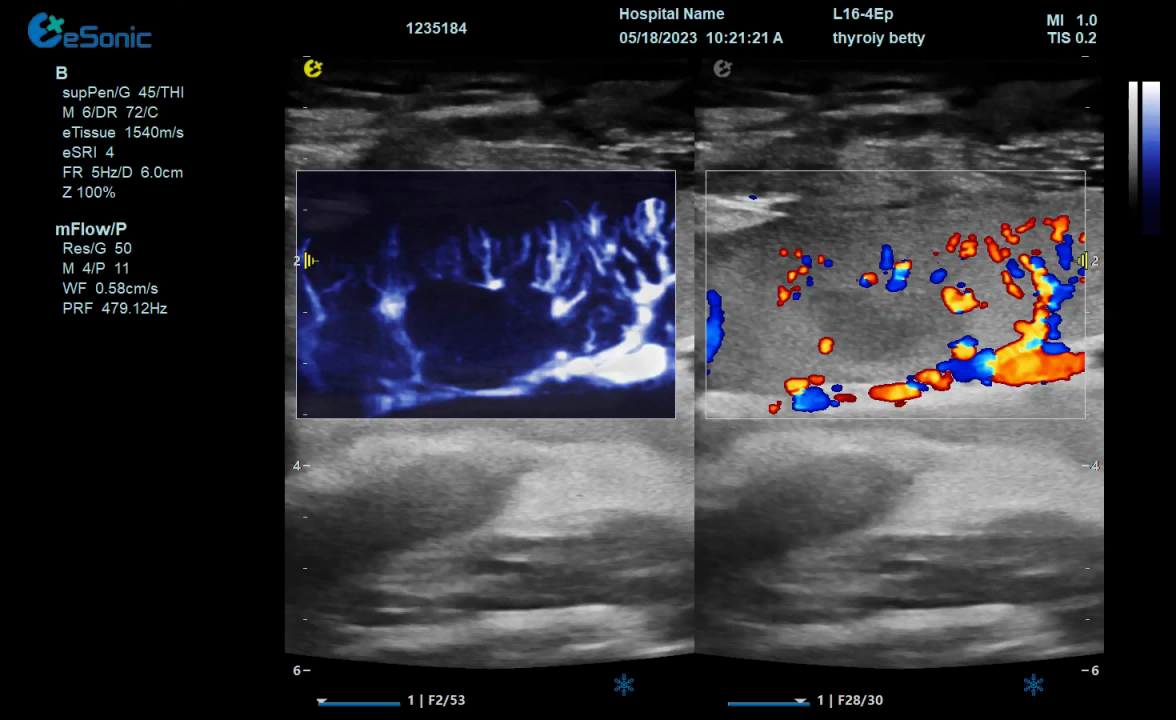

mFlow微血流显像技术,细节分辨率达100μm,支持频谱多普勒及VI血管指数定量。

mFlow子宫内膜下螺旋动脉

mFlow肾移植术后评估